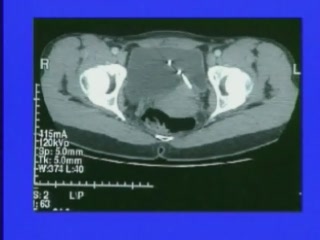

Laparoscopic Staging Procedu..

Laparoscopic Staging Procedu..

Douglas A. Levine, MD; Bhavana Pothuri, MD; Richard Barakat, MD; Nadeem Abu-Rustum, MD / CINE-MED